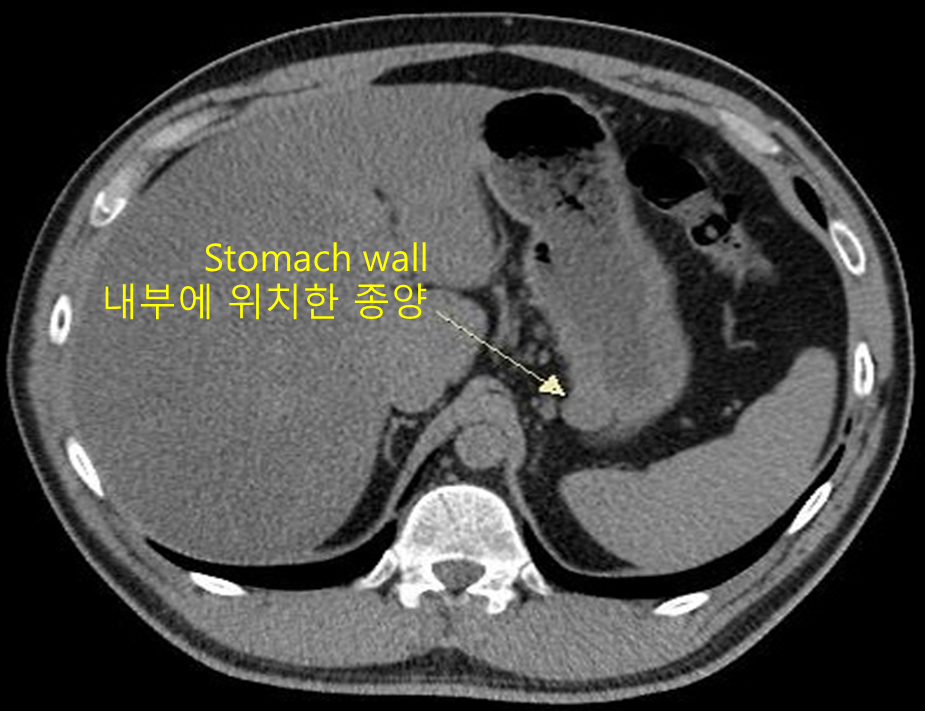

2) CT: 전이 여부 평가

점막 하층의 사이질 세포가 증식하는 종양이기 때문에 내시경상 표면이 점막으로 덮여 매끈해 보이는 것이 특징이라 추정진단을 잡는 데에는 어렵지 않다. 일반적인 gastric adenocarcinoma와는 달리 굳이 위의 많은 부분을 절제할 필요가 없으며, 쐐기절제술을 시행할 수 있다는 사실을 알아야 한다.